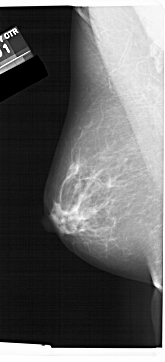

A_1456_1.RIGHT_MLO

LEFT_MLO LINES 6871 PIXELS_PER_LINE 3121 BITS_PER_PIXEL 12 RESOLUTION 43.5 NON_OVERLAY